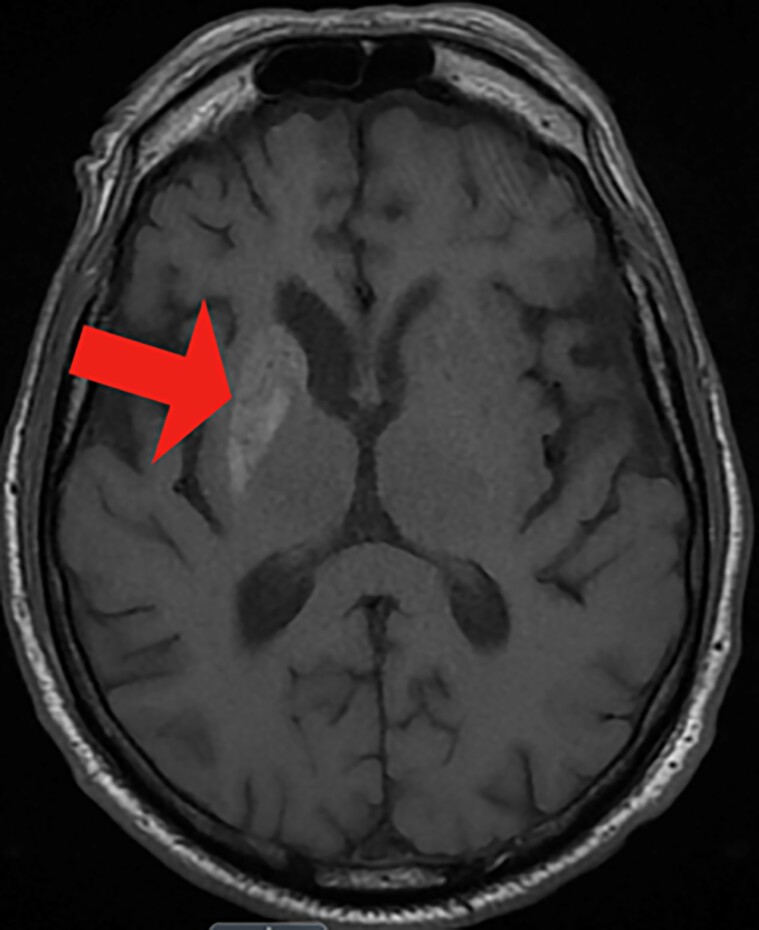

Nonketotic hyperglycemia chorea-ballismus (NKH-CB), a rare metabolic syndrome, arises as a secondary condition to hyperglycemia. It is marked by acute or subacute hemichorea-hemiballismus, hyperglycemic state, and unique reversible striatal abnormalities on neuroimaging. This case presents a 70-year-old Hispanic man with a significant medical history of cerebral vascular accidents, hypertension, bipolar disease, and uncontrolled type 2 diabetes mellitus. Notably, the patient was experiencing large-amplitude involuntary movements on his left side for the past 3 weeks. With resolution of hyperglycemia, the amplitude and frequency of the involuntary arm movements were absent. This case highlights the need for careful monitoring and tight control of blood glucose levels in patients with a history of diabetes, to prevent serious neurological complications such as NKH-CB syndrome. Prompt diagnosis through neurological evaluation, blood glucose level assessment, and neuroimaging techniques are critical in managing the symptoms effectively.

Abstract Image